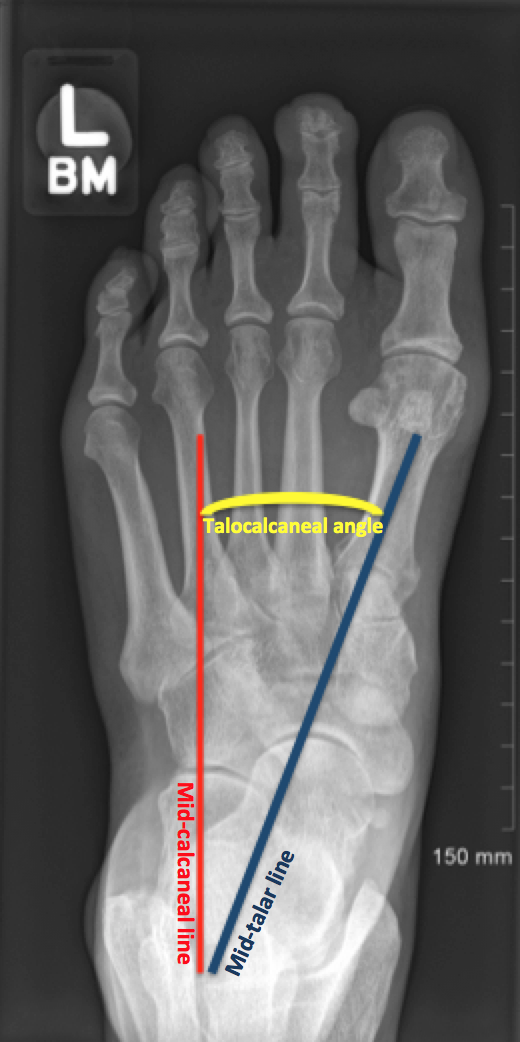

Talocalcaneal angle(30-55도, dorsiflexion lat시 25~50도) 이나 Talo-1st MT angle(5-15도), tibiocalcaneal stress lateral angle(10~40도) 를 시행해 볼 수 있습니다.

만곡족에서의 변화

Talocalcaneal angle은 AP에서 Kite angle 로 불리는데, 만곡족시 후족부가 내반될 경우 30도 이하가 됩니다. (cf. 외반일경우 55도 이상)

Talocalcaneal angle은 Lat 에서 감소하거나 음각이 되기도 합니다.

Talo-1st MT angle은 전족부의 내전을 평가하는 수치로, 만곡족에서는 음각 입니다.

Talocalcaneal index : 전후면 거종각 + 측면 거종각을 합한 수치로 (40도 이상 정상), 만곡족시 40도 이하가 됩니다.